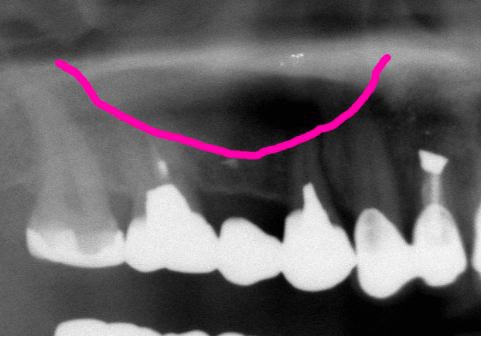

術前レントゲン